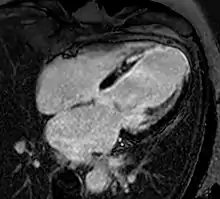

Myocardial infarction. Imaging in the 4-chamber plane. Left: Inversion recovery LGE sequence. Right: Corresponding cine sequence. This shows a chronic infarction with akinetic apex and transmural scar. Mitral regurgitation is also present.